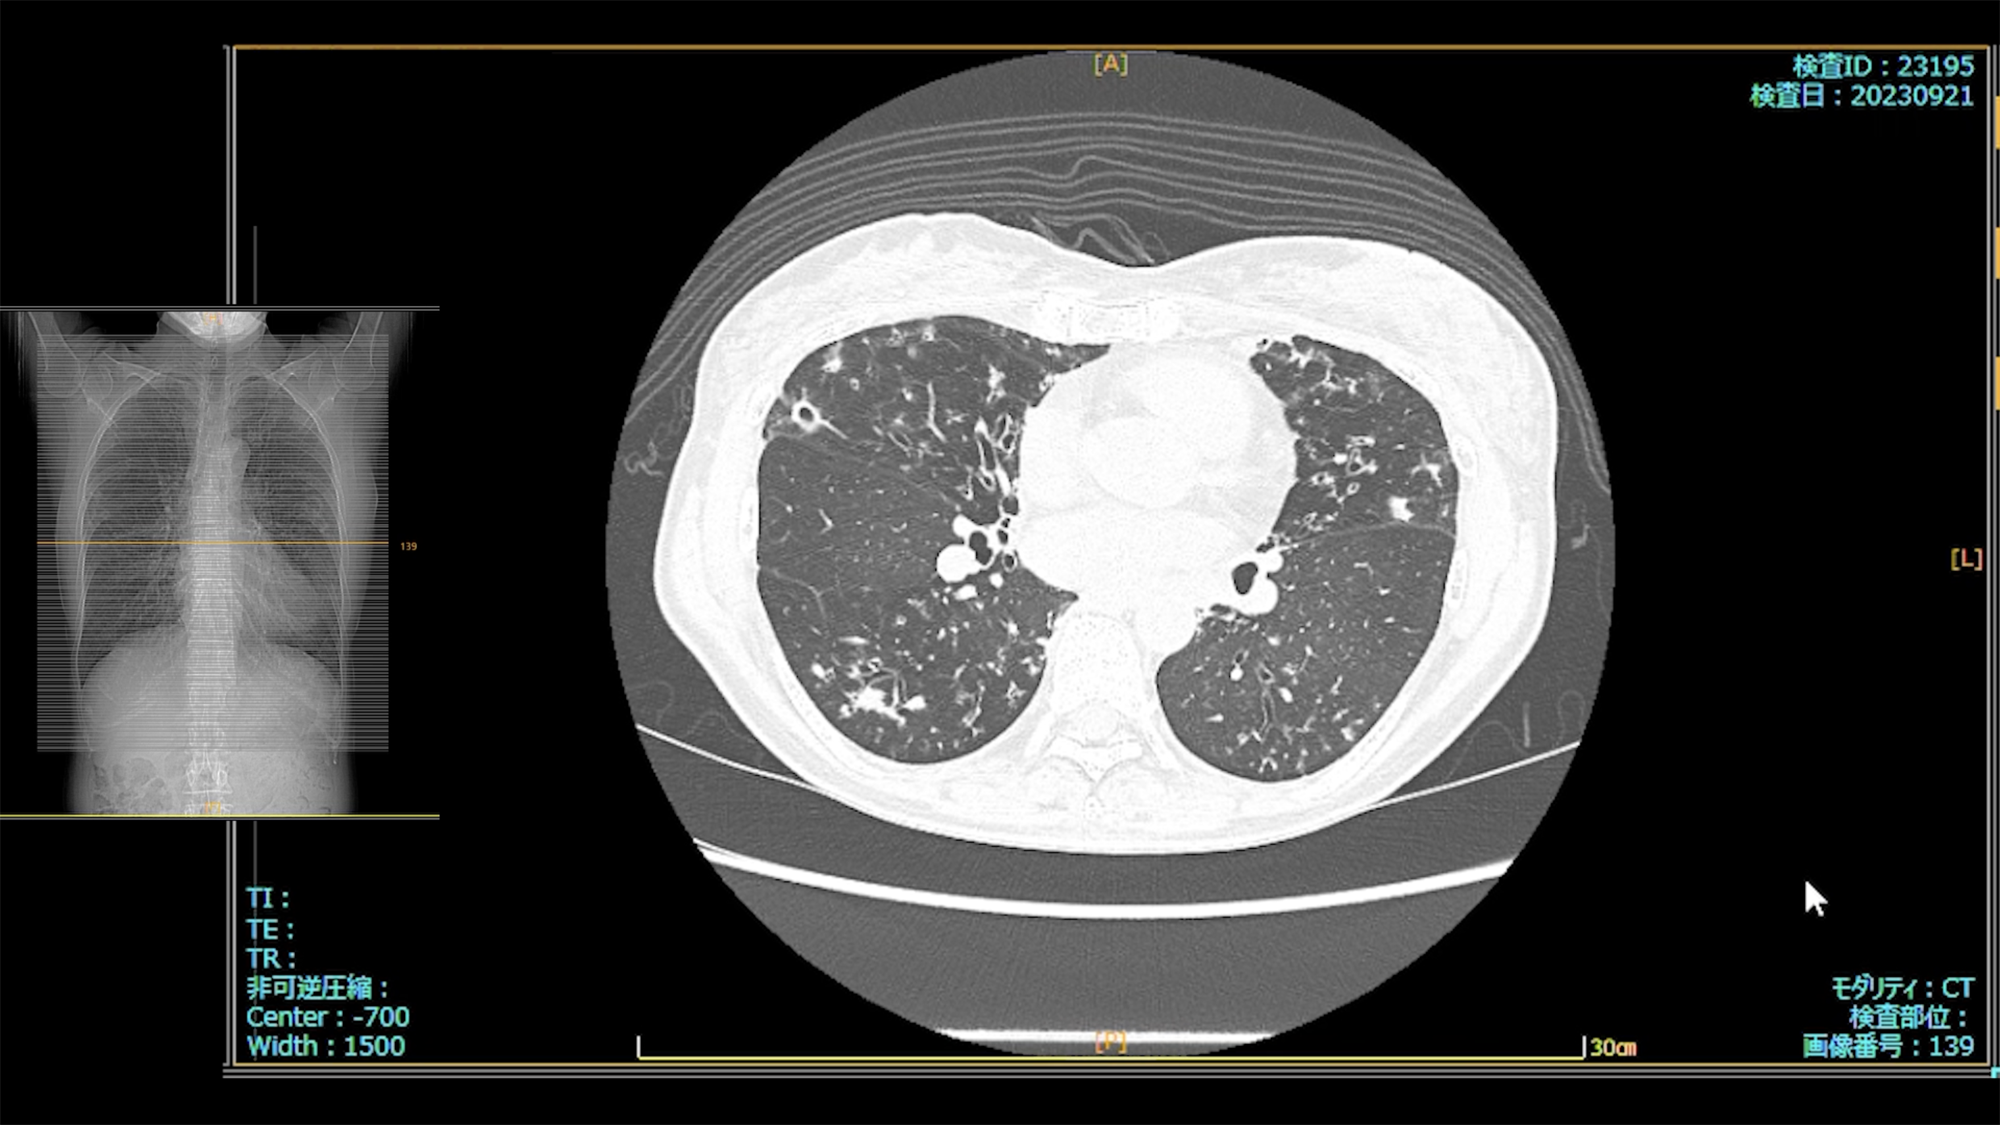

肺X線画像

- 2023.09.21 入院加療の必要ありと診断された画像(国立系病院)